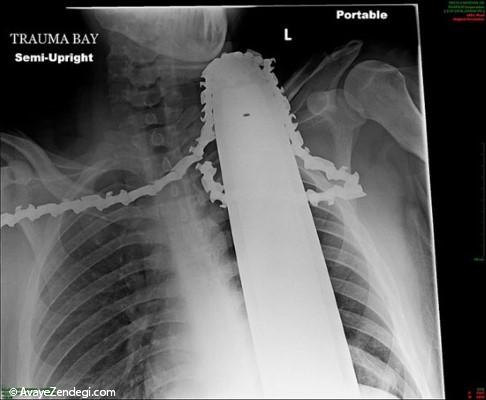

۳- این عکس اشعه ایکس از قفسه سینه، ارهای دندانهدار (اره برقی سبک) را نشان میدهد که در گردن و شانههای والتاین فرو رفته است. والتاین ۲۱ ساله مشغول هرس درختان بود که ناگهان اره او به او برخورد کرد و تیغههایش در بدن او فرو رفت. همکارانش او را از بالای درخت پایین آوردند و به بیمارستانی در پیتزبورگ پنسیلوانیا انتقال دادند.